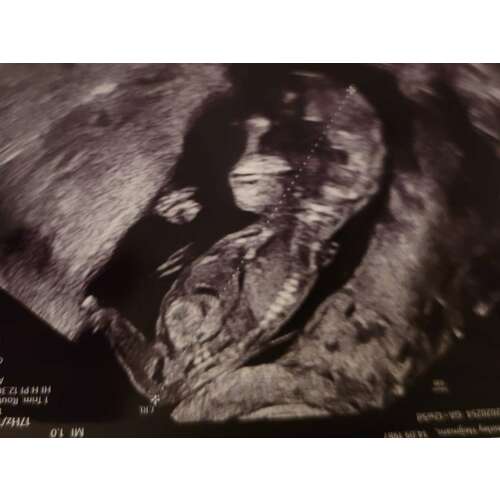

Hier ben ik 11+6, denk net iets te vroeg om het te kunnen zien. Wellicht dat iemand wel al wat kan zien. Ben zo benieuwd ☺️